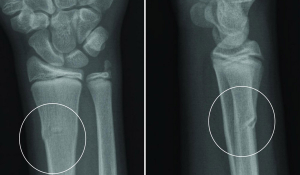

Перелом саме променевої кістки є найпоширенішим травматичним пошкодженням передпліччя.

У 90% випадків причиною перелому є падіння на витягнуту руку.